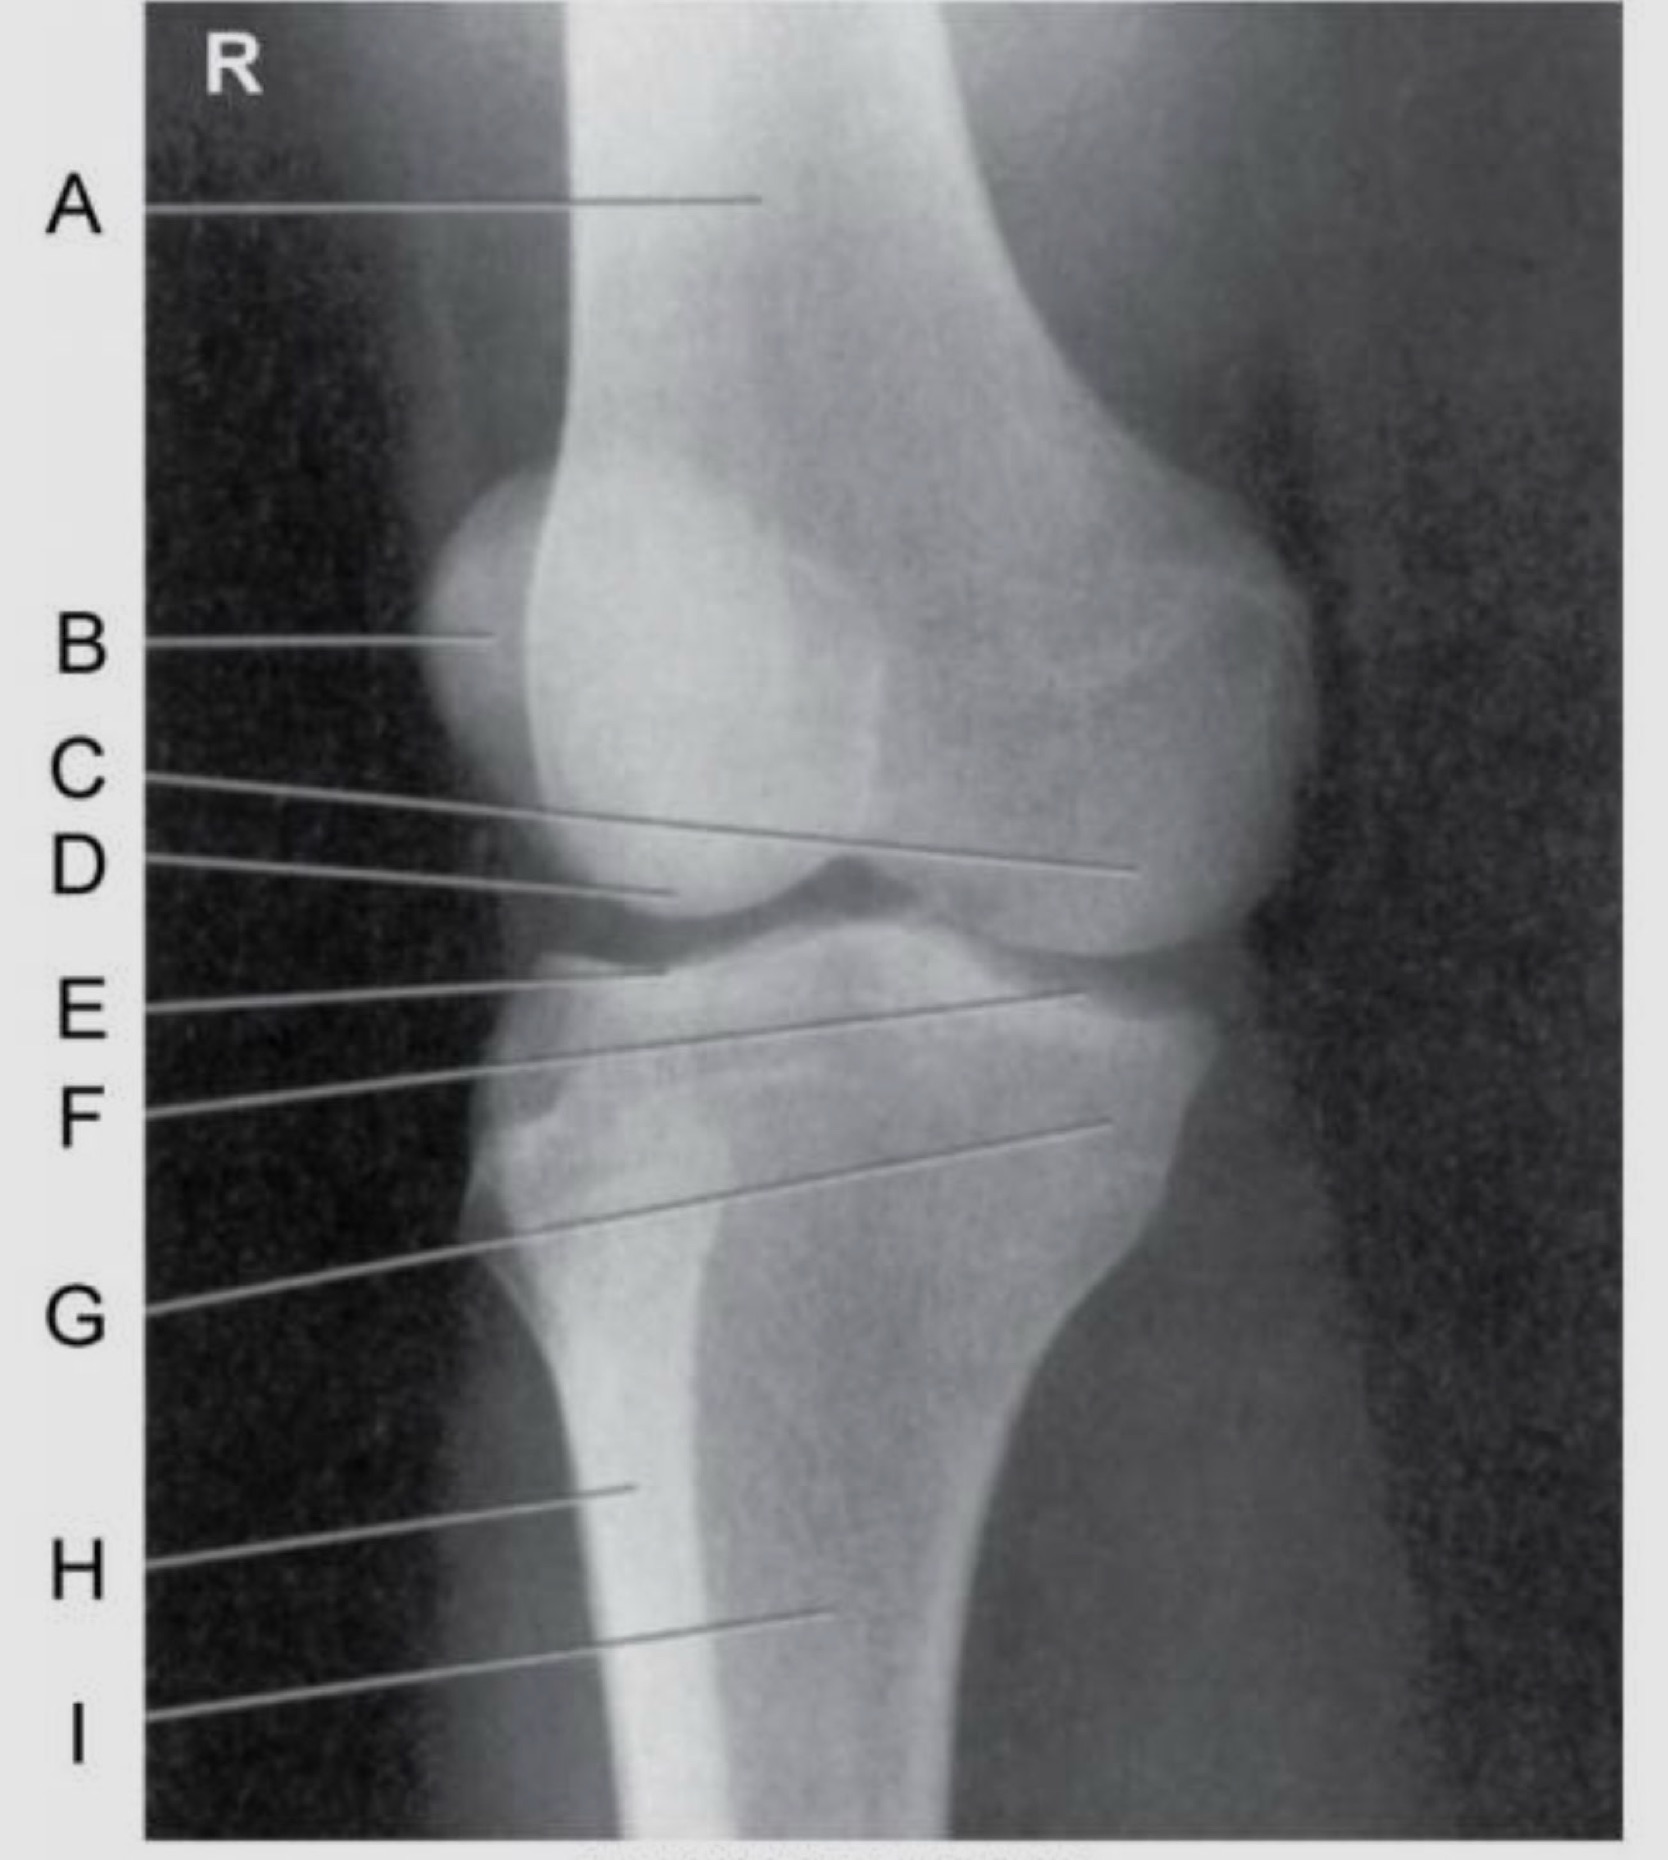

Name the projection.

Should it be repeated, if so why?

AP Lateral (external) Oblique

No.

Label the image.

A) Femur

B) Patella

C) Medial femoral condyle

D) Lateral femoral condyle

E) Lateral tibial plateau

F) Medial tibial plateau

G) Medial tibial condyle

H) Fibula

I) Tibia